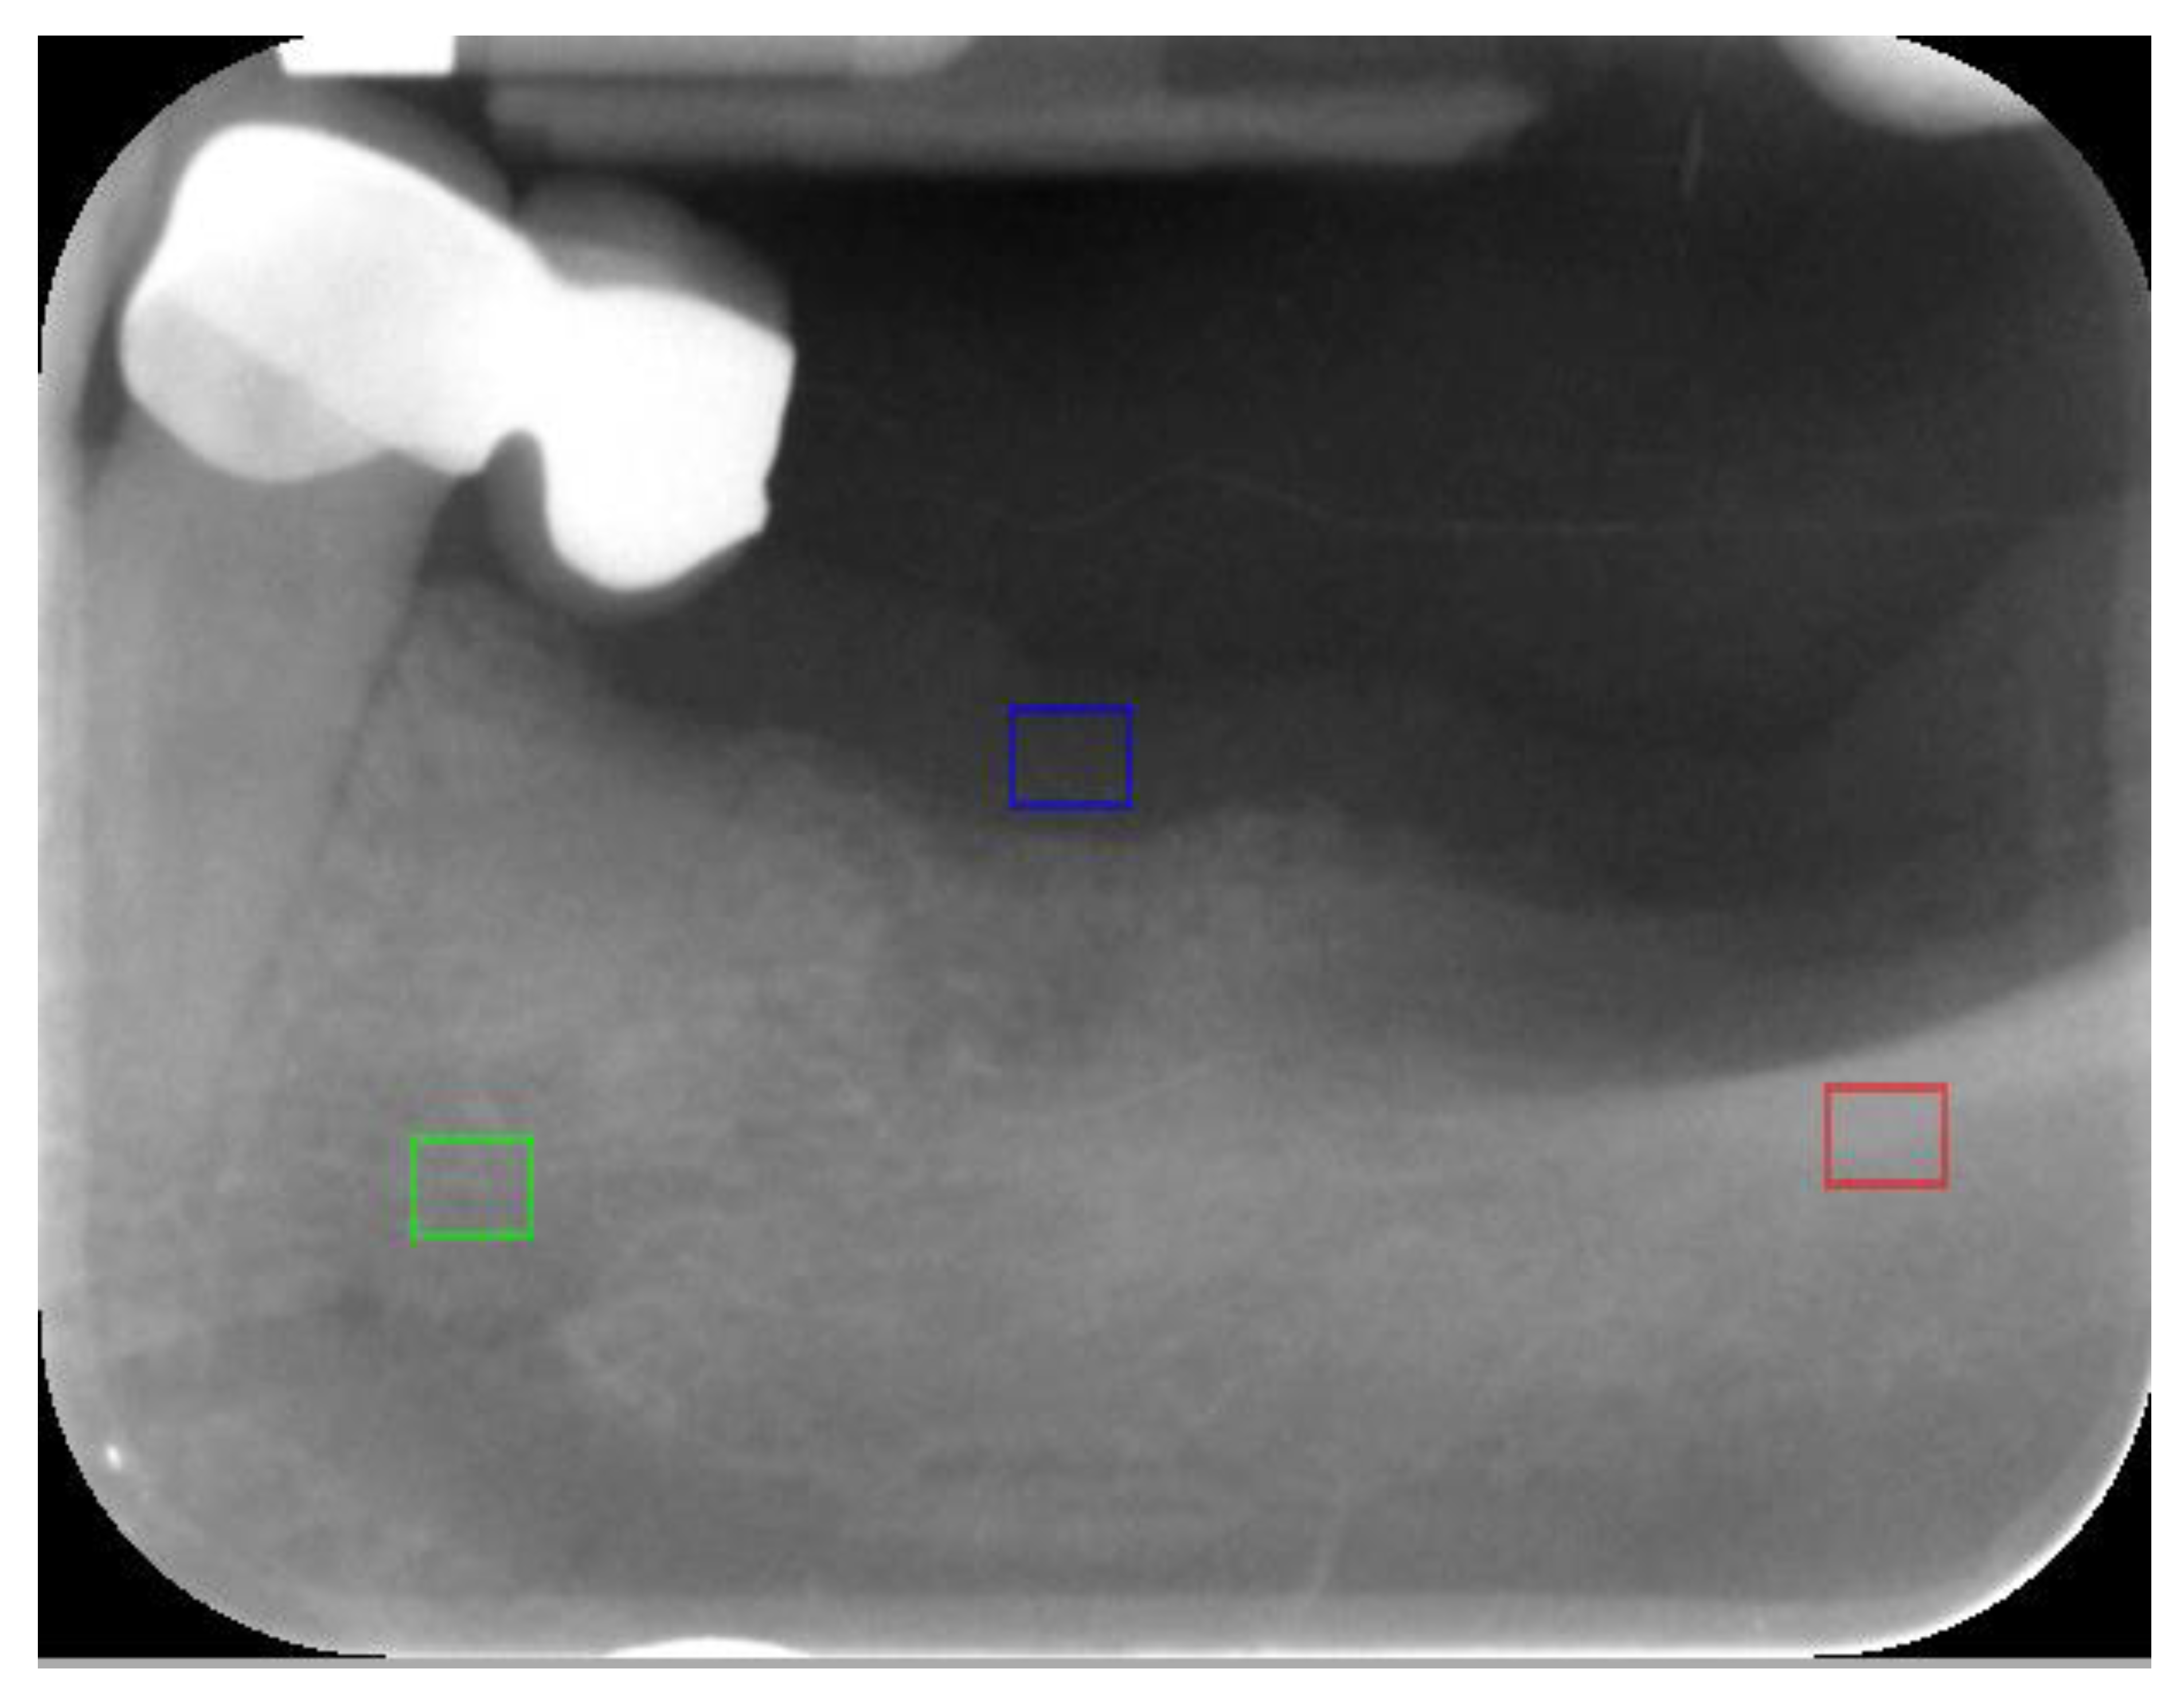

2. Materials and Methods